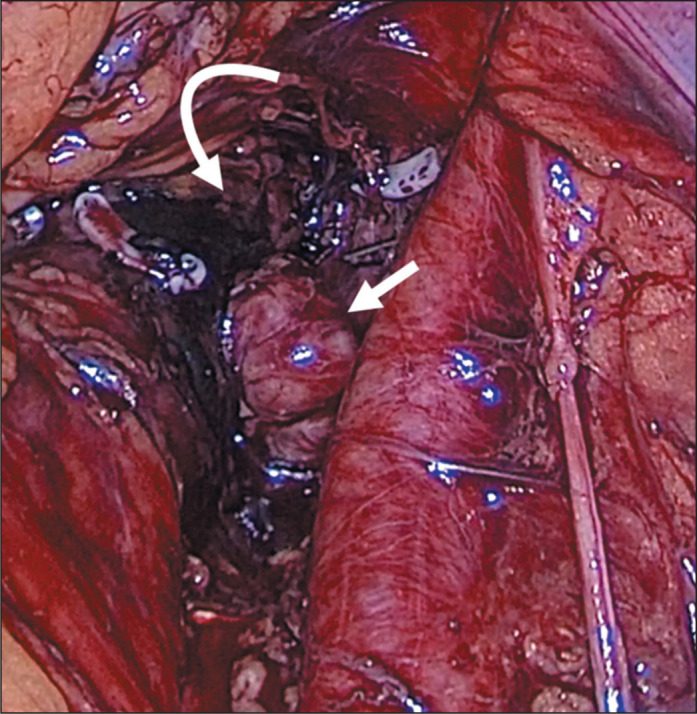

Computed tomography-guided preoperative charcoal tattooing in patients with recurrent prostate cancer after prostatectomy and undergoing pelvic salvage lymphadenectomy.

Abstract Image